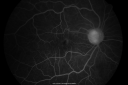

67-year-old man has proliferative diabetic retinopathy in both eyes with vitreous hemorrhage in the left eye. He has had pan retinal laser in the left eye. The vitreous hemorrhage has been there for greater than two years and his vision is still hazy. He takes Lumigan in both eyes for his glaucoma.

VISUAL ACUITY: OD 20/40, OS 20/40. IOP: OD 12, OS 11. The right eye has a posterior chamber intraocular lens in good position, as does the left eye.

OD: Vertical C/D ratio is 0.8. There is neovascularization on the inferior and superior pole of the optic nerve.

The macula is dry. There are ischemic changes in the periphery including ghost vessels.

OCT SCAN: The OCT scan of the right eye shows the macula to be flat. The left eye shows a stable macular pucker. Photos confirm clinical findings.

FLUORESCEIN ANGIOGRAPHY: Fluorescein angiography shows leakage from the neovascularization on the nerve in the right eye and in the inferotemporal of the macula in the left eye and also the peripherals sweeps in the right eye show significant non perfusion, especially inferonasally.

1. PROLIFERATIVE DIABETIC RETINOPATHY – BOTH EYES

2. NON CLEARING MILD VITREOUS HEMORRHAGE – LEFT EYE

3. GLAUCOMA

DISCUSSION: I explained to the patient with the proliferative retinopathy in the right eye, he has a high risk of vision loss, especially given that he has blood already in his left eye. I would like to protect the right eye from a similar fate. I started pan retinal laser in the right eye today